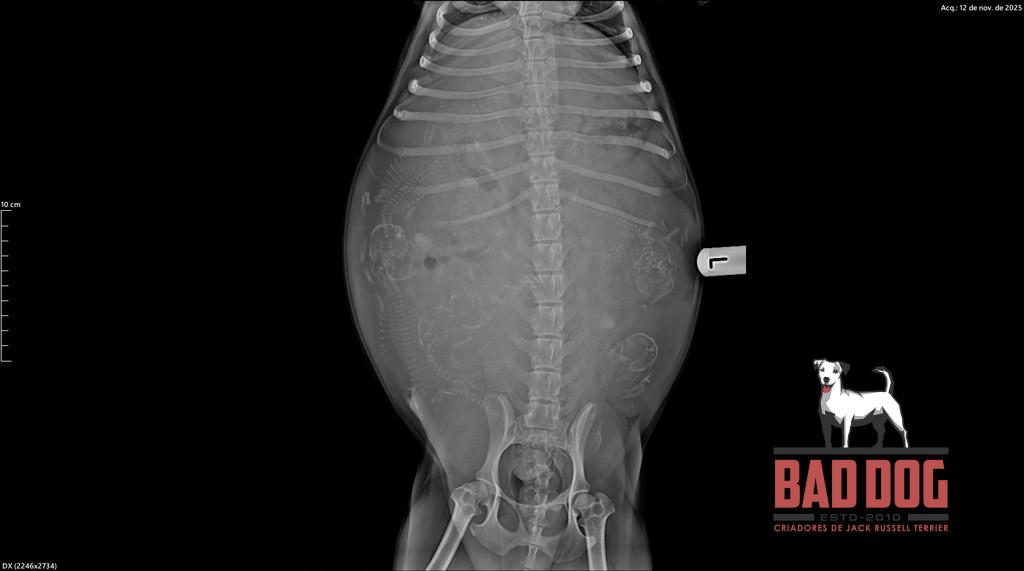

PHI2_oliva-rx phi2_litter_2